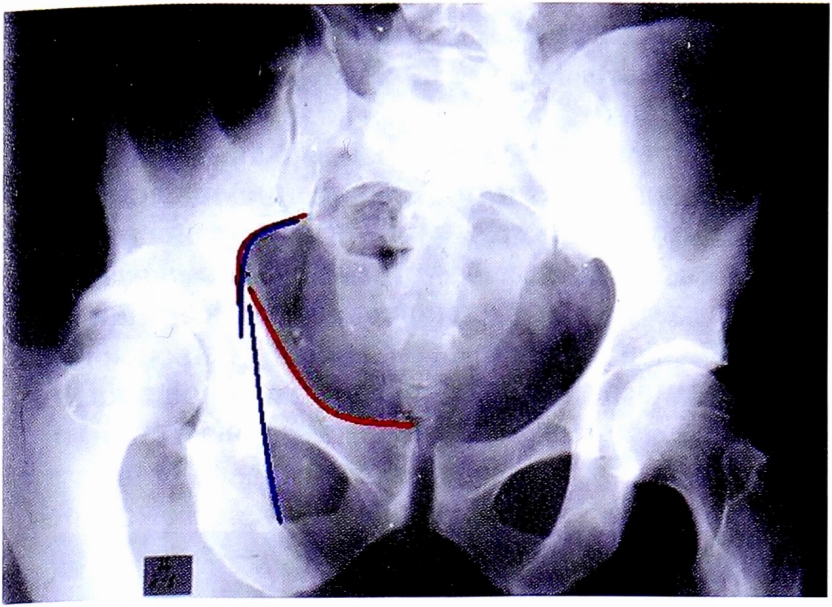

Каудальная обзорная рентгенограмма (Inlet) позволяет выделить зоны, которые соответствуют анатомическим структурам вертлужной впадины: передняя стенка и передняя колонна (рис. 9), задняя колонна (рис. 10).

Рис. 9. Контуры передней колонны на рентгенограмме в каудальной проекции и на схеме.

Fig. 9. Anterior column brim on inlet pelvic X-ray and on schematic pelvis.

Рис. 10. Контуры задней колонны на рентгенограмме в каудальной проекции и на схеме, также определяются контуры большой и малой седалищной вырезок.

Fig. 10. Posterior column brim on inlet pelvic X-ray and on schematic pelvis.